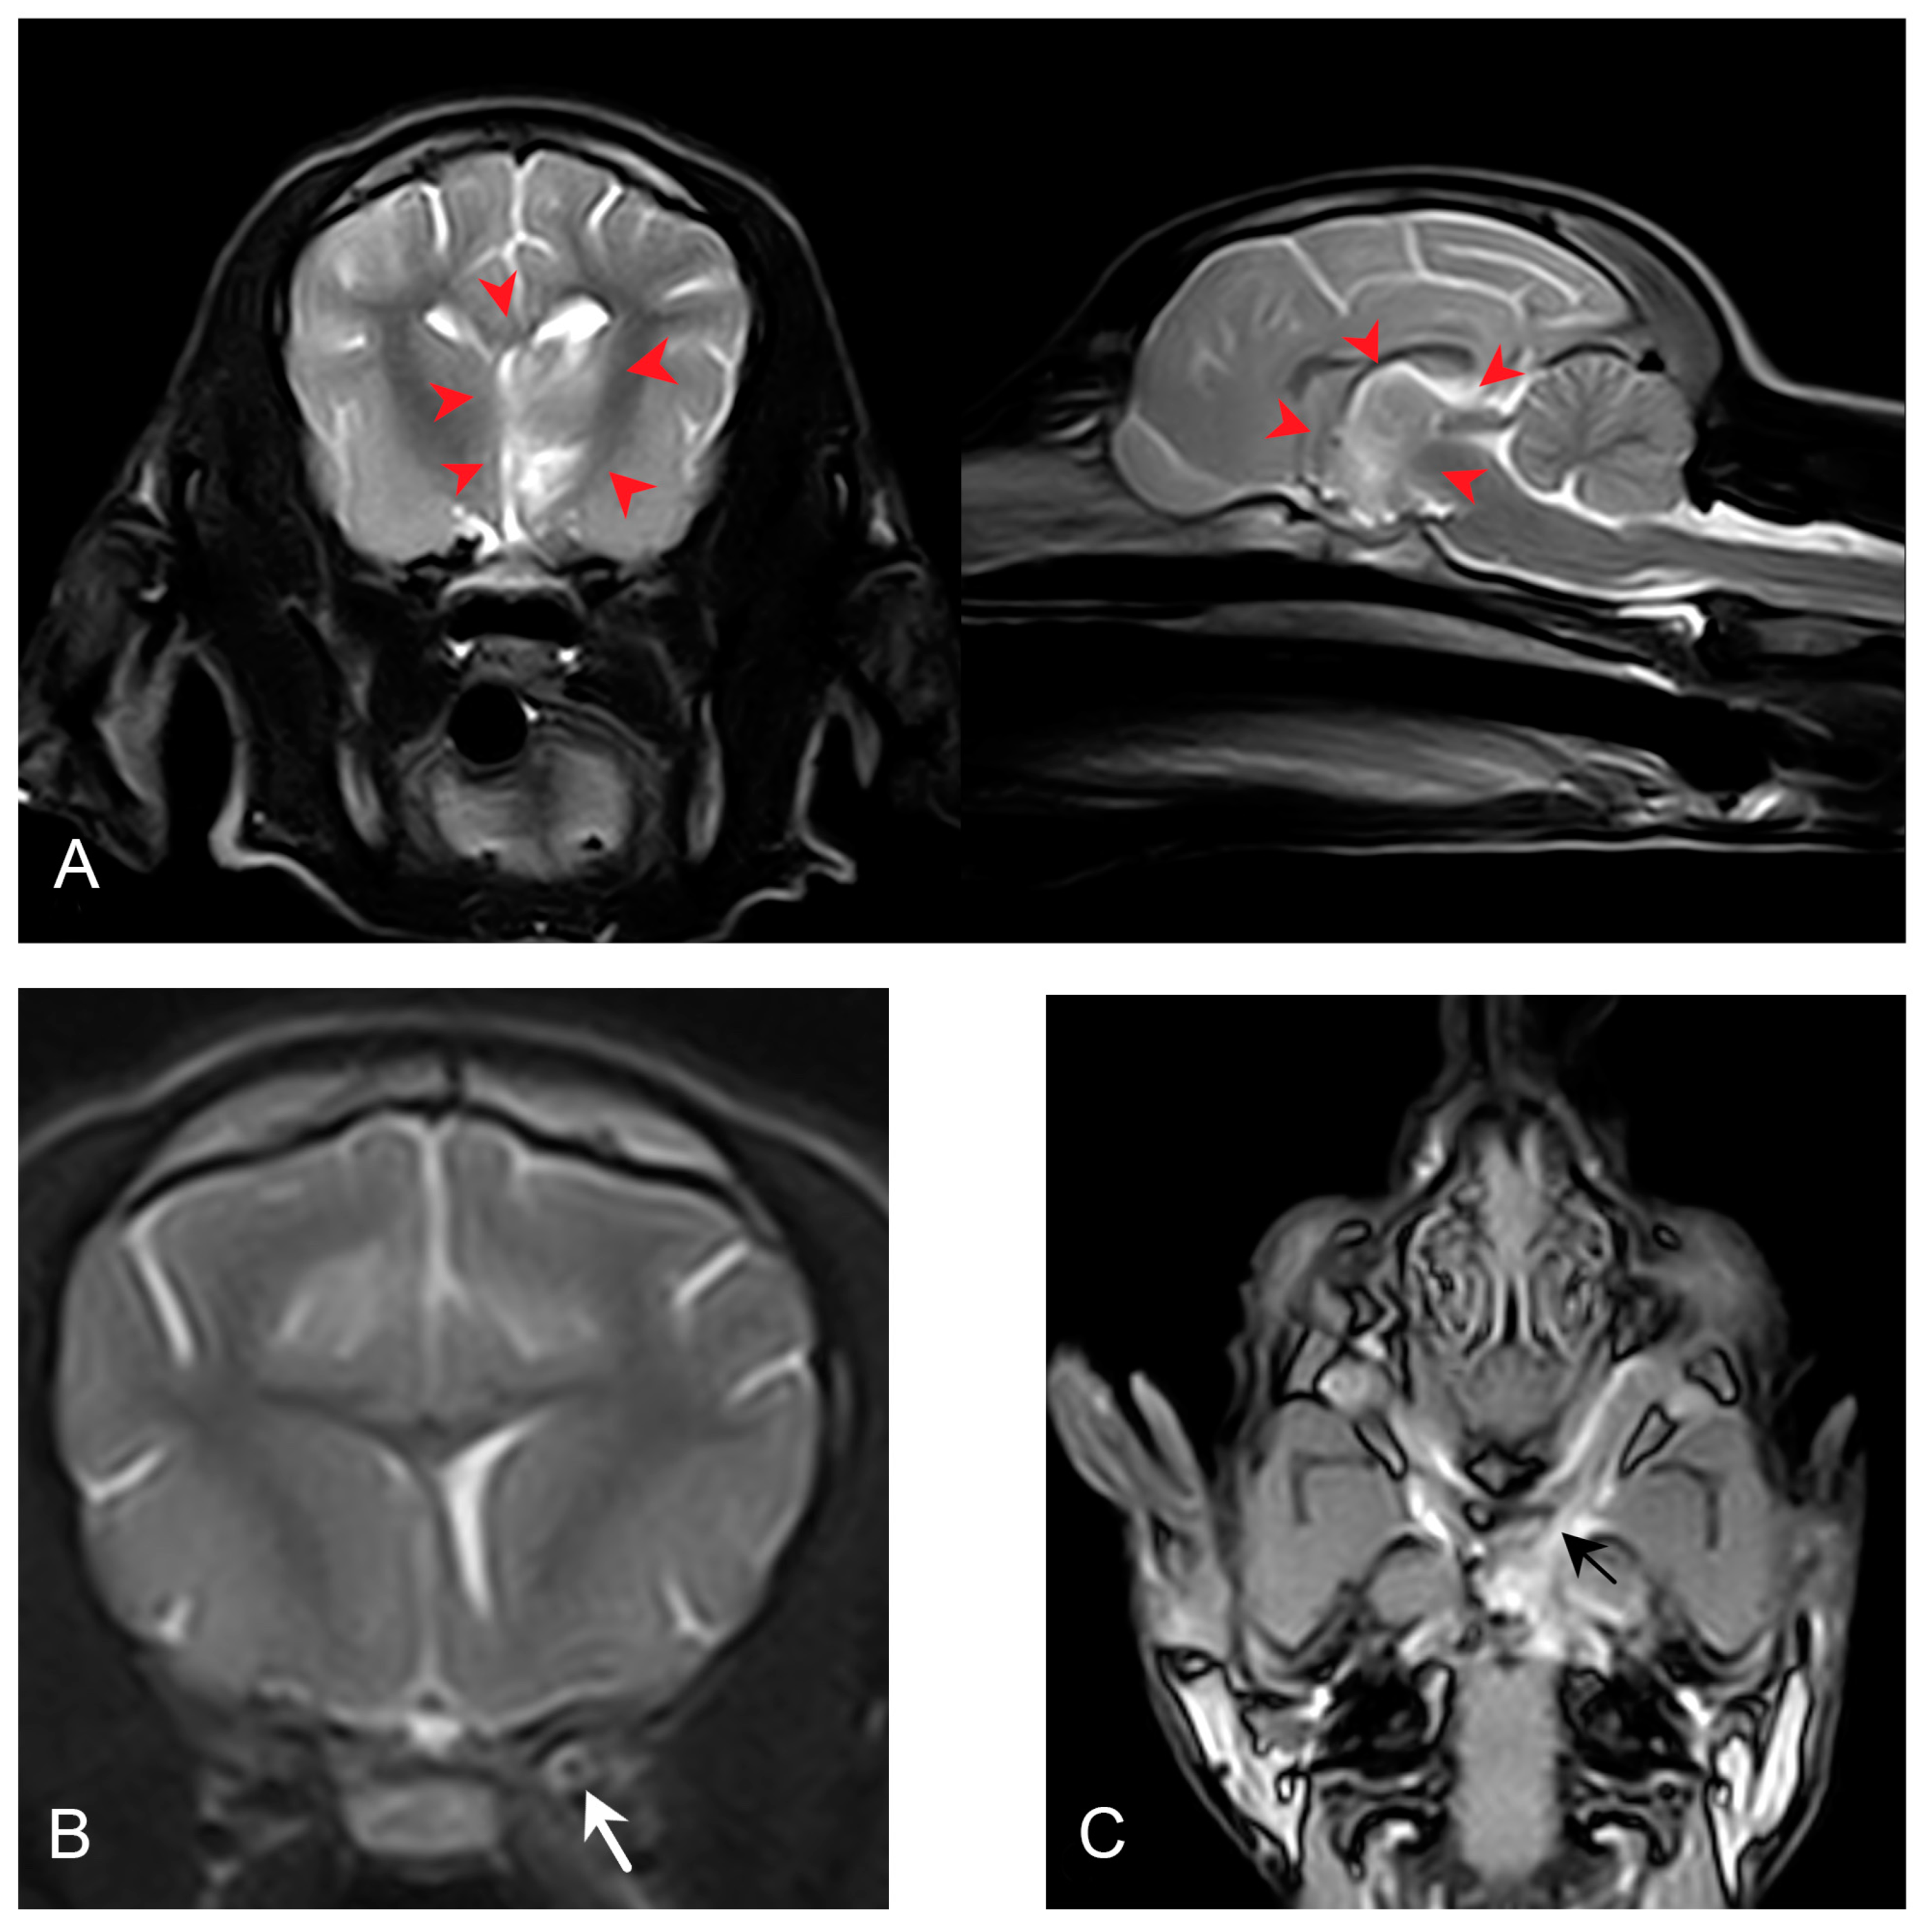

The haematology (IDEXX ProCyte Dx, IDEXX Nordics, Solna, Sweden), complete blood count, and biochemistry (IDEXX Catalyst One, IDEXX Nordics, Solna, Sweden) at presentation (day 2) were unremarkable, except for a mildly increased C-reactive protein (CRP) (39.4 mg/L, range 0.0–10.0 mg/L). Magnetic resonance imaging (MRI) and cerebrospinal fluid (CSF) analysis were performed two days after presentation (day 4). During this time, the dog was treated with prednisolone (prednisolonacetate, CP Pharma, Burgdorf, Germany) at 2 mg/kg subcutaneously once daily and received intravenous fluid therapy (Ringeacetate, Fresenius Kabi, Uppsala, Sweden) at 3 mL/kg/h). Treatment was initiated due to a suspicion of immune-mediated meningoencephalitis, based on the clinical presentation suggesting a multifocal localisation. Over the next two days, the dog showed clinical and neurological improvement (improved mentation and disappearance of the head turn), and CRP was decreased to 16.5 mg/L (reference range: 0.0–10.0 mg/L). Magnetic resonance imaging (MRI) of the brain was performed using a standard protocol (T2-weighted, T1-weighted, fluid-attenuated inversion recovery (FLAIR), and T1W3D pre–postcontrast) with a 0.2 Tesla permanent magnet (Esaote Vet-MR Grande, Esaote, Genoa, Italy). The MRI revealed a left-sided intraparenchymal, diffusely outlined abnormality involving the thalamus, part of the hypothalamus, and the rostral part of the mesencephalon (Figure 1). The abnormality was heterogeneously hyperintense in T2W, with streaks of increased T2W signal and focal areas of reduced T1W signal, which were not contrast-enhancing. Besides the intraparenchymal abnormalities, the meninges surrounding the piriform lobe and the ventral part of the left temporal lobe showed contrast enhancement. The left optic nerve was wider than normal, was hyperintense in T2W, and was contrast-enhancing (Figure 1).

Figure 1.

Sagittal (right) and transverse (left) T2-weighted MRI images demonstrating part of the diffusely outlined intraparenchymal T2W hyperintensity within the left thalamus, hypothalamus, and rostral part of the mesencephalon (red arrowheads). The abnormality is heterogeneously hyperintense in T2W, with streaks of increased T2 signal. There is a mild midline shift but no signs of transtentorial herniation (A). Transverse T2-weighted MRI image demonstrating the hyperintensity of the left optic nerve (white arrow) (B). Dorsal postcontrast 3DSST1 MRI image demonstrating contrast enhancement of the left optic nerve (black arrow). The left optic nerve is wider than normal, and the rostral limit of the changes is rostral to the left optic canal and extending into the optic chiasm, confluent with severely enhancing meninges around the left piriform lobe, as well as the ventral part of the left temporal lobe (C).